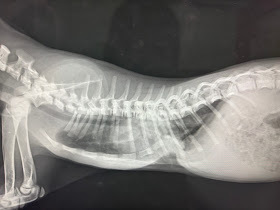

漏斗胸の例

生まれつき胸がへこんでいる子達がいます。 胸骨が曲がってしまっていて、肺の広がりが悪いので呼吸が苦しくなってしまう事があります。ギブスやプレートで骨の角度を変える手術が適応になります。